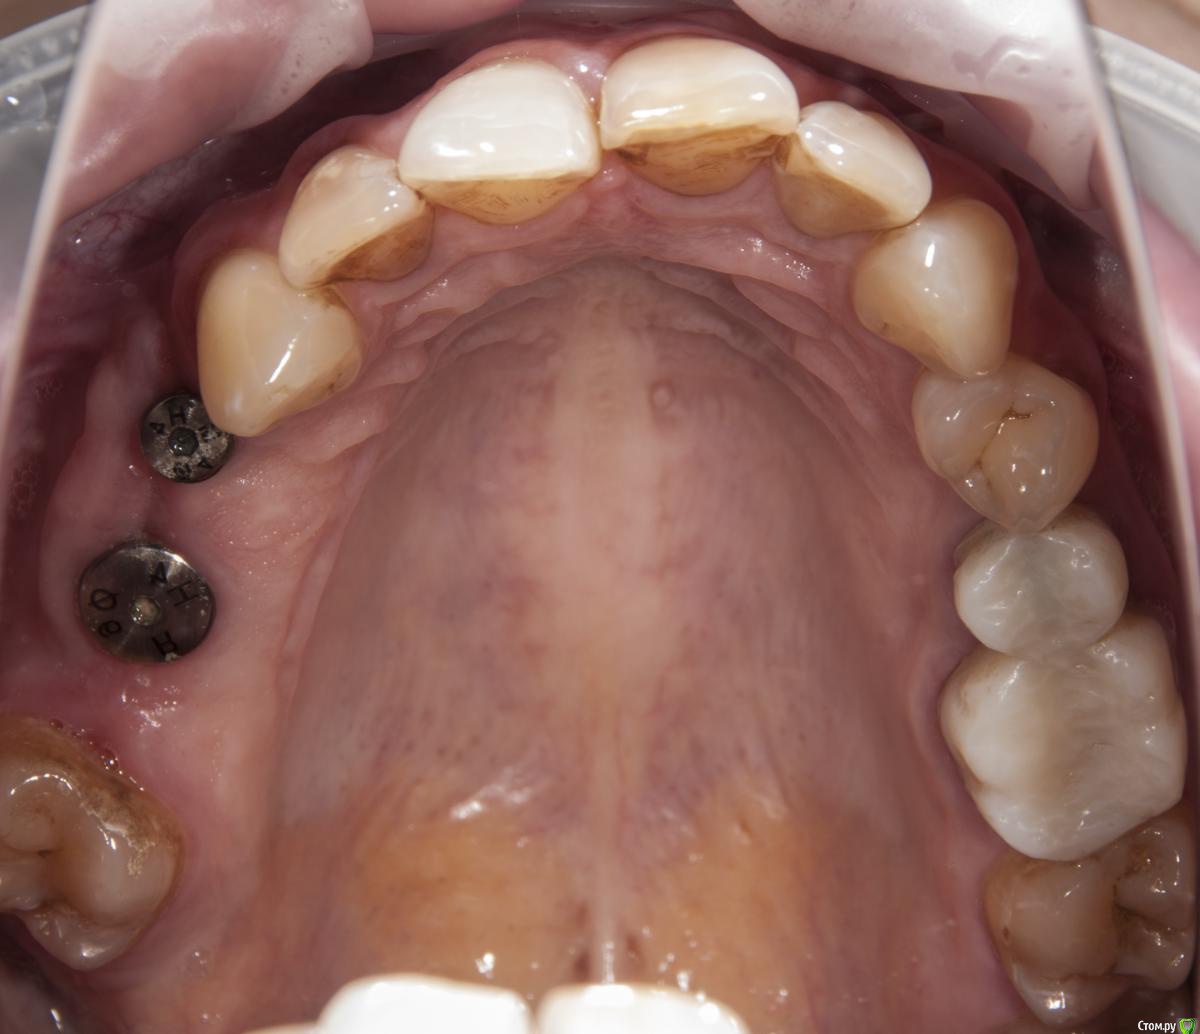

kamranchick Опубликовано 4 мая, 2018 Поделиться Опубликовано 4 мая, 2018 Добрый день Уважаемые коллеги, имеются проблемы с ортодонтией в нашем славном городе.Какие будут предложения по кейсу, сколько визитов и по ценникам, можно в личку.Пациент готов ездить в другие городаP.S пациент тоже будет следить за ходом этой ветки))) Ссылка на комментарий

krokomot Опубликовано 4 мая, 2018 Поделиться Опубликовано 4 мая, 2018 А импланты уже успели установить. 1 Ссылка на комментарий

kamranchick Опубликовано 4 мая, 2018 Автор Поделиться Опубликовано 4 мая, 2018 А импланты уже успели установить.Как видите вопросов много конечно, но что можно предложить имея такую картину. Ссылка на комментарий

krokomot Опубликовано 4 мая, 2018 Поделиться Опубликовано 4 мая, 2018 в данной ситуации конечно шляпа у пациента, если совсем все плохо, можно бы, ло бы просанировать для начала, снять скан, затем, поробовать на инвизилайнерах решить основные проблемы в окклюзии , затем тотальное протезирование. Идейка конечно не айс, но всё же выход. Ссылка на комментарий